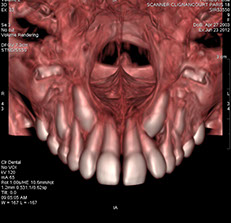

Scanner dentaire

Le scanner dentaire permet entre autres d'explorer des anomalies liées au développement des dents, de repérer les foyers d'infection ou des kystes autour des racines dentaires. Il permet également de préparer un implant métallique en vue de remplacer une dent manquante.

Le scanner dentaire se fait à l'aide d'un appareil équipé d'un tube à rayon X. Lors du déroulement de l’examen, le tube du scanner est en rotation autour du patient qui est placé sur un lit mobile. L'appareil permet alors de réaliser une imagerie en "coupes", utile à l'exploration des dents et des arcades dentaires. Grâce à un traitement informatique et à ces clichés, il est possible de reconstruire des images en 2D ou 3D (modélisation dans l’espace).